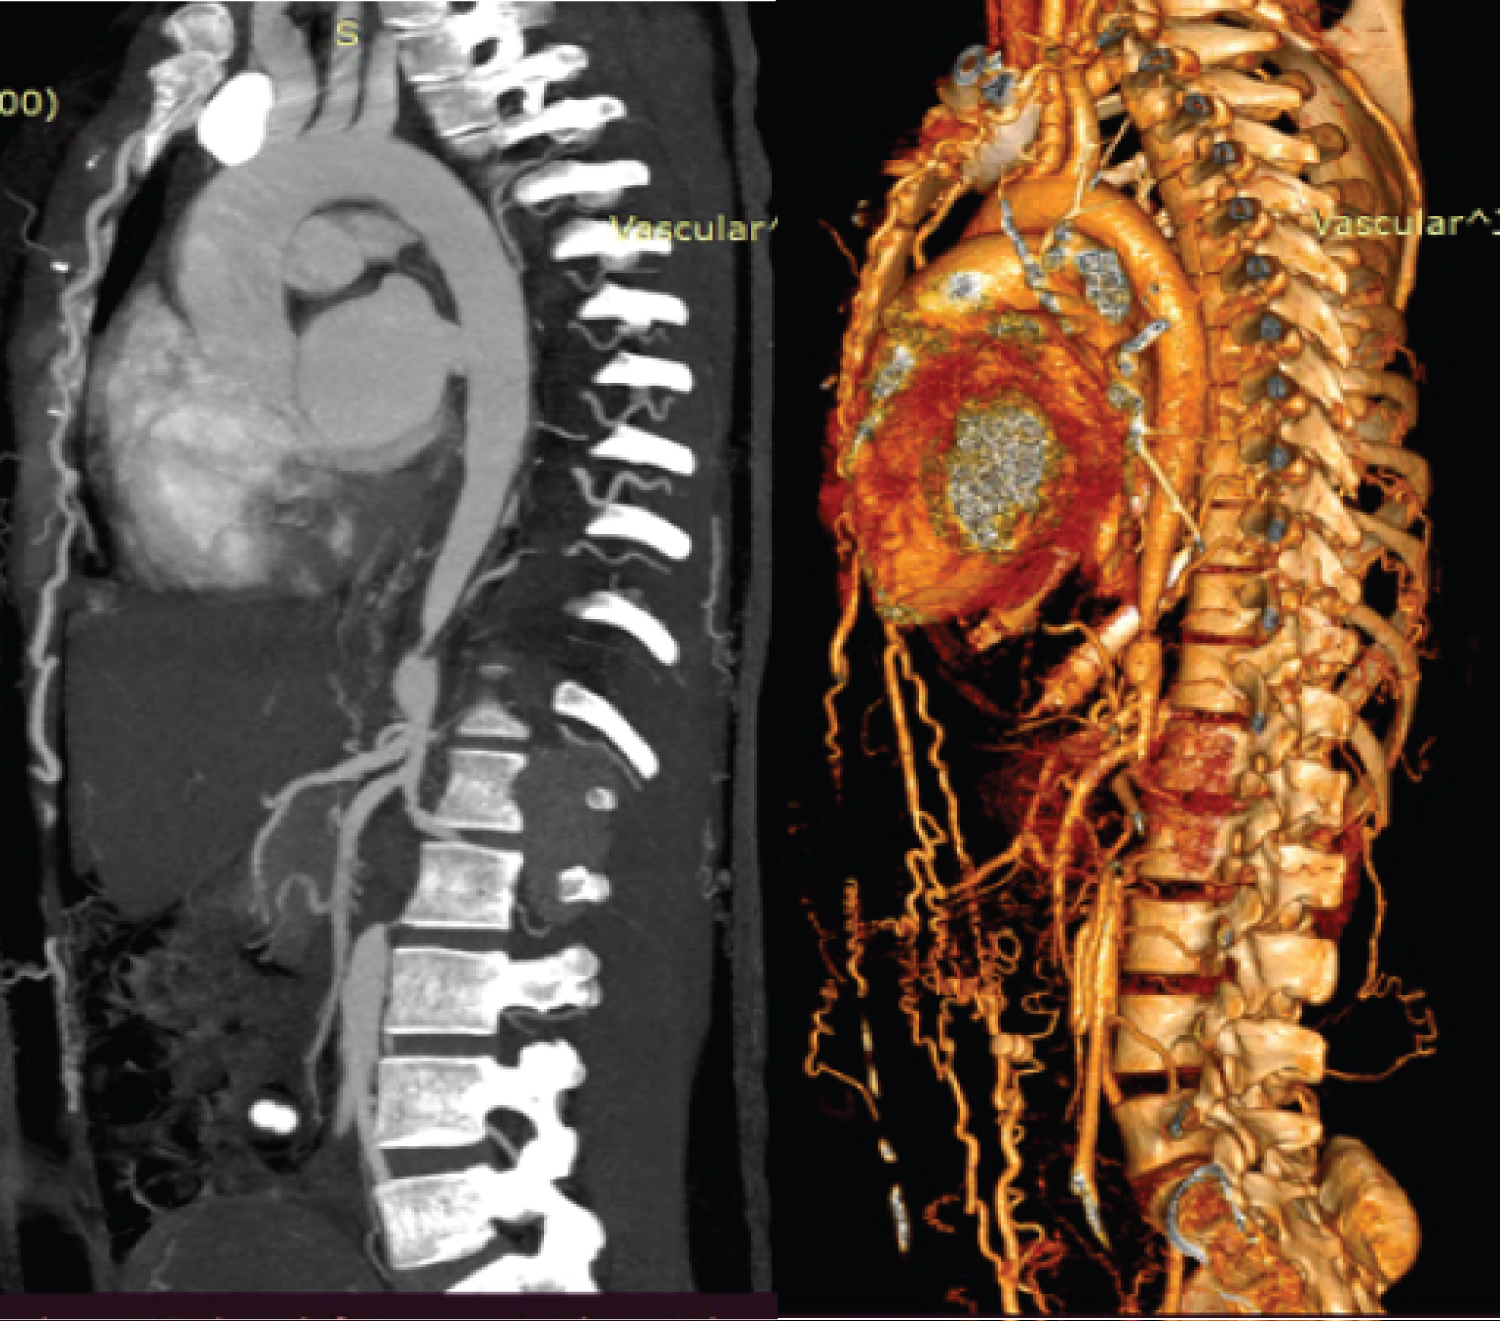

Post MTP, the USG showed no evidence of retained products of conception. A CT Aortogram revealed a short segment of significant luminal narrowing (3.7 cm) in the suprarenal segment of the descending aorta, complete 100% occlusion (length 3.9 cm) in the infrarenal abdominal aorta, suggestive of Mid Aortic Syndrome. Prominent mesenteric and abdominal collaterals were noted, SMA, IMA and bilateral renal arteries were normal (Figure 1).

Figure 1: Left side image- CT Aortogram showing short segment of significant luminal narrowing (3.7 cm) in the suprarenal segment of the descending aorta, complete 100% occlusion (length 3.9 cm) in the infrarenal abdominal aorta; Right side image- 3D reconstruction image of the same findings. View Figure 1